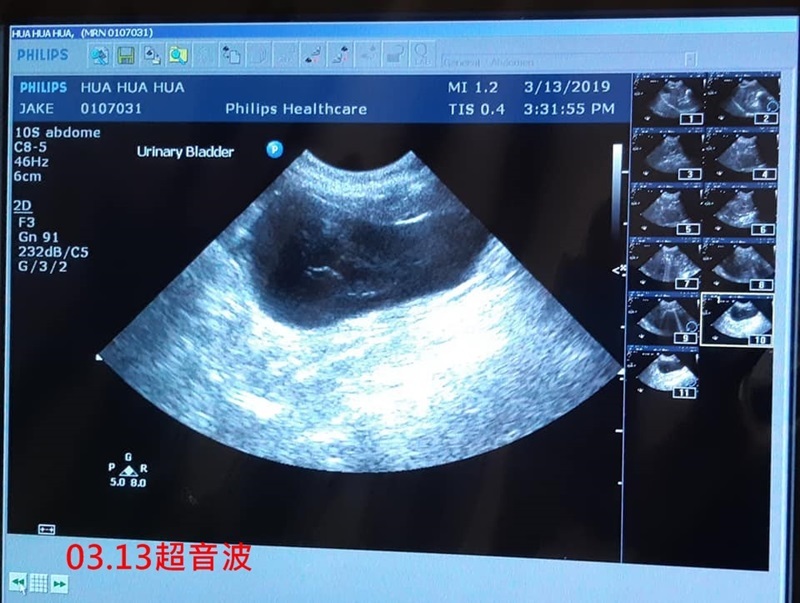

3/13 花嬸 沐恩林文傑醫師

一、說明:

花嬸3/13一早流口水,臨時約診沐恩。

二、看診情形

血檢結果並無胰臟炎,

超音波檢查,胃腸腎沒有異樣,膀胱看到較多較大的尿渣,林醫師認為這與花嬸流口水、拉肚子並無關聯。